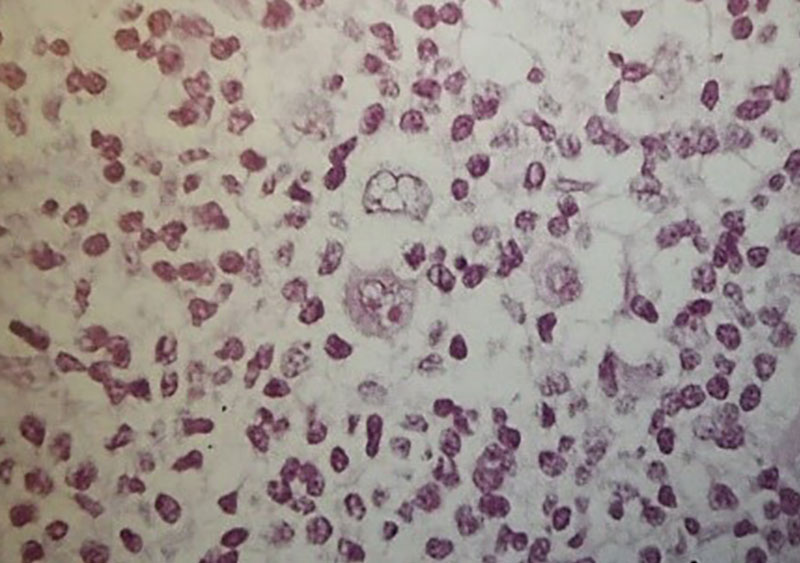

1. تفسیر شما از گسترش خون محیطی بیمار ( شکل 55a) چیست؟ علت این موارد کدام است؟

در گسترش خون محیطی بیمار، افزایش تعداد ائوزینوفیلها دیده میشود. مقدار طبیعی کمتر از 109×0.4 بر لیتر است.

2. نظر شما دربارهی بیوپسی غده لنفاوی (شکل 55c,55b) چیست؟

نمونهبرداری از غده لنفاوی (بیوپسی) نشاندهندهی ارتشاح سلولی مختلط (mixed cellular infiltrate) همراه با حضور سلولهای بزرگ و شاخص Reed–Sternberg است.